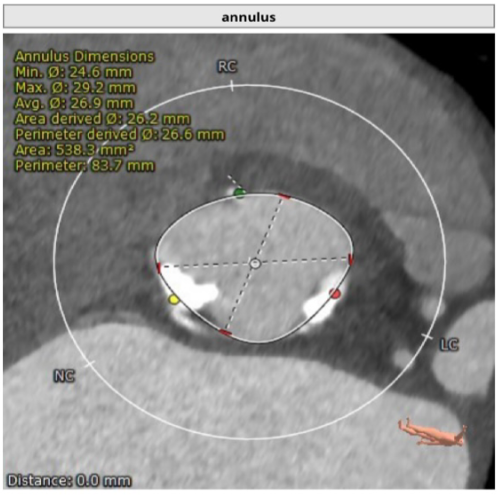

CTA主动脉根部解剖:患者为二叶瓣,重度钙化,瓣环平面可见钙化,可见钙化延伸至左室流出道,右无、左无均可见融合,以右无融合为明显,冠脉高度尚可。升主动脉最宽处为超过 45mm,心脏角度约:49度。

Annulus Dimensions ——26.6 mm

LVOT——29.1mm

Sinus——32.6*34.5*32.7mm

STJ——31.4 mm

升主最宽处:39.8mm

心脏角度:49°

该病例为:Type1型二叶式主动脉瓣,重度钙化并严重增厚,法式窦结构大,双冠脉开口高度良好,主动脉瓣环夹角可,非横位心,主动脉弓夹角锐利,弓距可,左心室腔增大,推荐右侧股动脉为主入路,左侧辅助入路,建议使用20F戈尔血管鞘,备SNARE;推荐跨瓣角度LAO26°CRA5°左右,推荐使用22mm球囊预扩,角度为LAO22°CRA2°(左冠切线位);推荐预装L26瓣膜,释放角度RAO21°CAU35°(左右重合),释放高度推荐较高位(瓣环下0-2mm)。